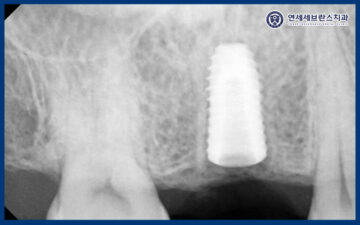

25.08.29

<식립 후 한달 체크>

그리고 임플란트는 식립 후 약 한 달간의

초기 치유 기간이 매우 중요한 시기로,

이 시기에 임플란트와 주변 골 사이의

안정적인 결합이 형성되기 때문에

세심한 경과 관찰이 필요합니다.

그래서 환자분께 내원하시도록 안내드렸고,

엑스레이 촬영을 통해

곡반정동임플란트와 주변 골이 안정적으로

잘 유지되고 있는지 확인했습니다.